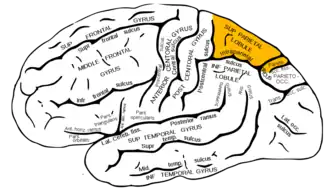

Lateral surface of left cerebral hemisphere, viewed from the side. (Superior parietal lobule is shown in orange.) | |